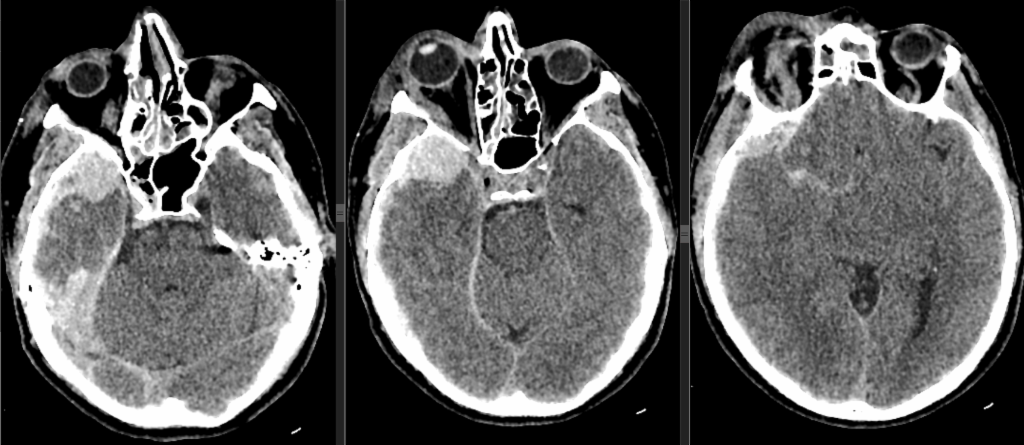

Субдуральная гематома диагностика